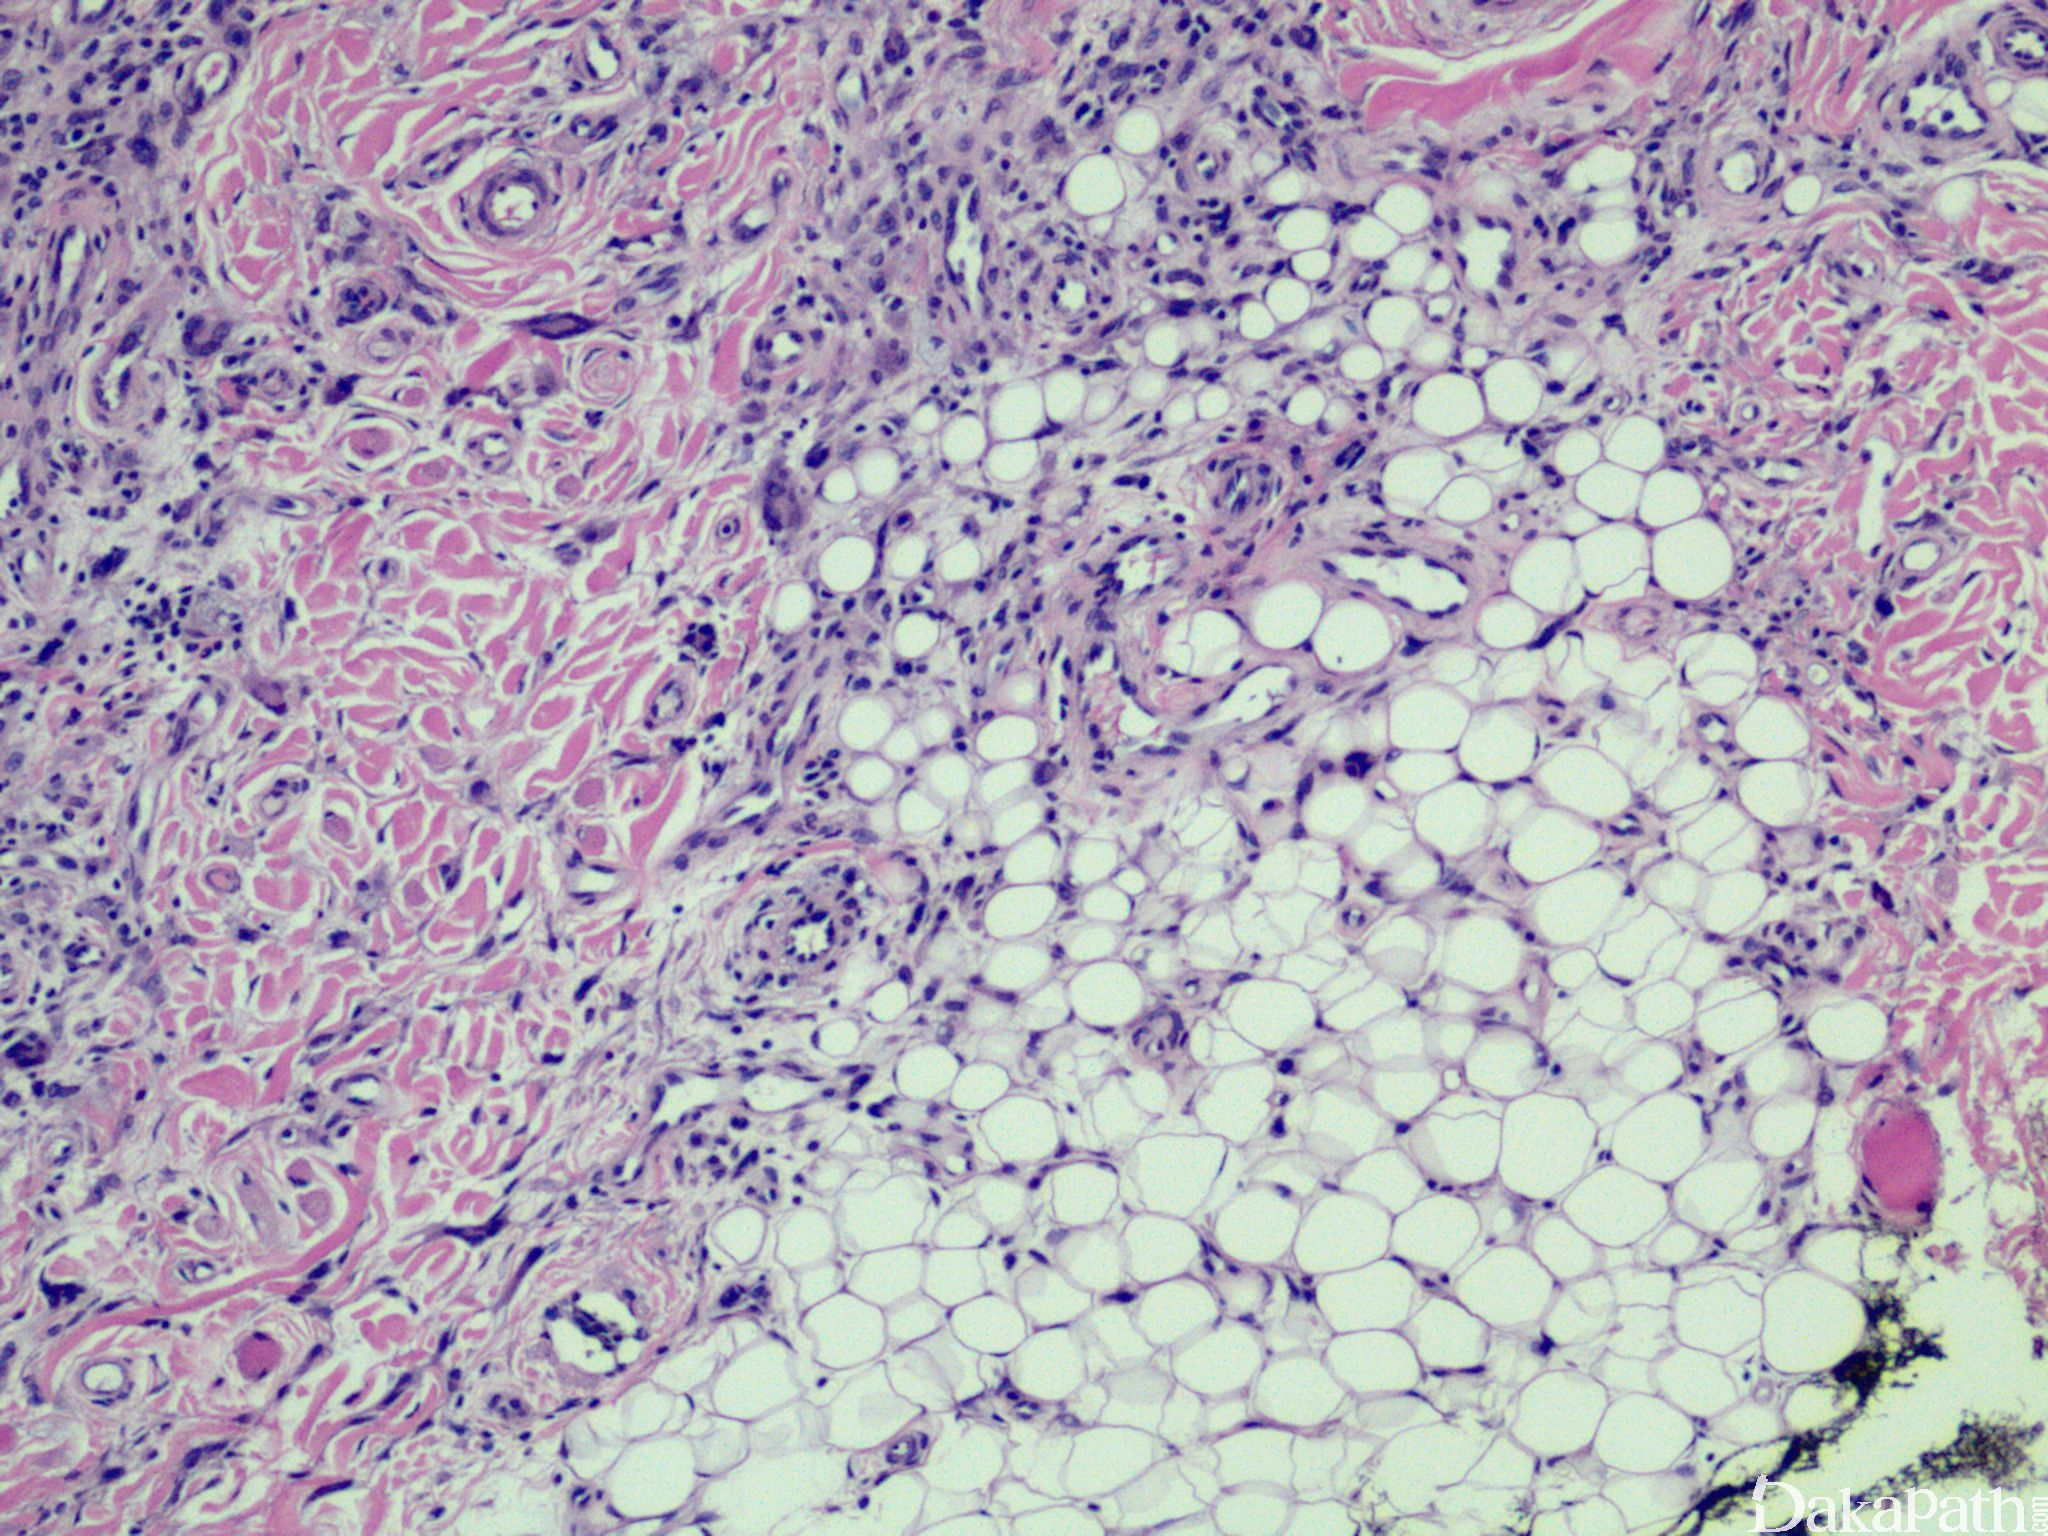

黄色肉芽腫

xanthogranuloma